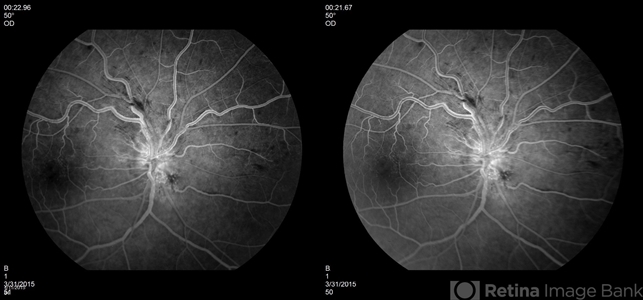

- background diabetic retinopathy (BDR), diabetes, fluorescein leakage, optic nerve edema, optic disc swelling, disc leakage, stereo pair

- Optic Nerve Edema and Leakage on fluorescein angiography in this 48-year-old patient with a 10 year history of diabetes. 50 degree stereo photo fluorescein angiogram.